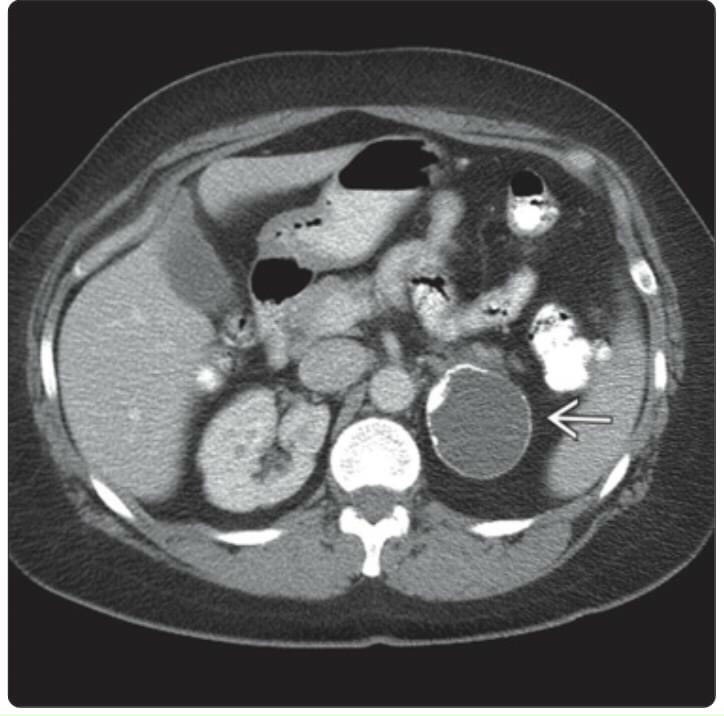

Hình ảnh nang tuyến thượng thận

Hình ảnh nang tuyến thượng thận

Hình ảnh nang tuyến thượng thận

Hình ảnh nang tuyến thượng thận